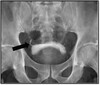

What pathology is seen here?

Phleboliths